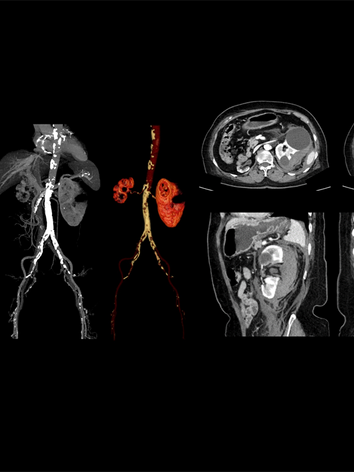

uCT 820

The uCT 820 scanner is equipped with advanced AI technologies and designed with a patient-centered philosophy. It provides comprehensive tissue characterization, minimizes radiation exposure, enables rapid volumetric imaging, and streamlines exam setup for enhanced patient throughput. uCT 820 delivers an exceptional premium CT examination experience for both you and your patients.

With an AI-empowered workflow that covers the entire process from scanning to diagnosis, the uCT 820 scanner provides an excellent CT examination experience that is both highly intelligent and precise. You can now deal with challenging clinical scenarios with ease.